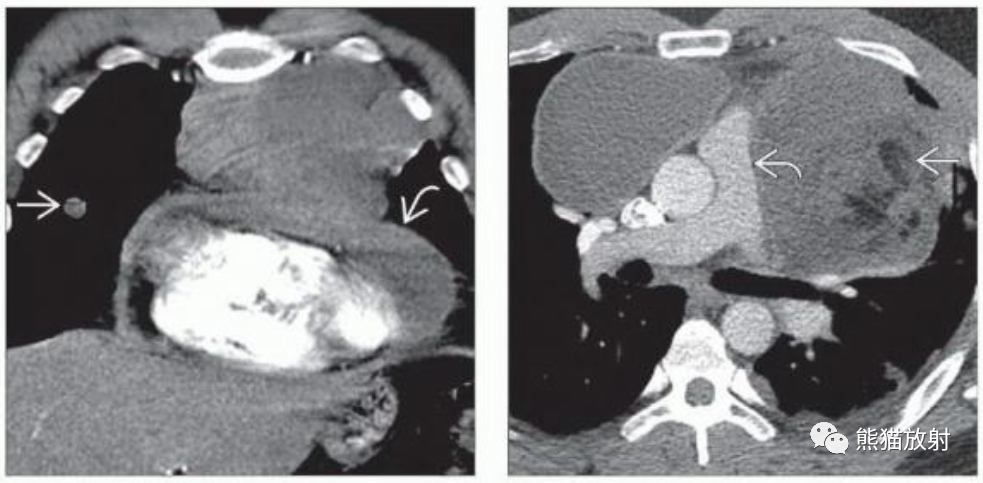

(左)41岁男性,纵隔卵黄囊瘤。冠状CECT显示前纵隔巨大不均质肿块,心脏移位,心包增厚,心包积液和右肺转移。

(右)31岁男性,轴位CECT显示大的不均匀的纵隔肿块,对肺动脉干有占位效应或侵犯。虽然活检证实为胚胎癌,但脂肪的存在提示混合型恶性生殖细胞瘤。